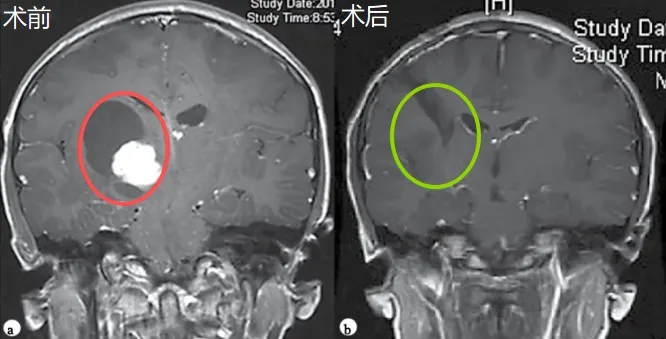

红色为术前,绿色为术后,显示肿瘤全切,脑组织复位,无脑出血、脑水肿等损伤。

等到医生看清状况,内心不免更加焦灼,因为如如的肿瘤位于右侧丘脑,怀疑为胶质瘤,且皮质脊髓束(负责人体肢体运动的神经传导束)已然受压,并导致了脑室扩大。这些特点都加大了手术的风险和难度。

没想到,也正是这场手术,为他们的女儿带来了生机。鲁特卡教授如术前预期的那样顺利完成全切,且未造成任何神经功能缺损。组织病理学诊断结果显示,如如患上的是毛细胞星形细胞瘤,无疑是另一个好消息。